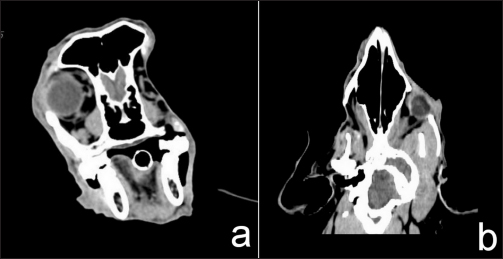

After radiation

After complete radiation, the dog had normal clinical signs with some hair loss at the radiation site. The CT images showed no detectable recurrent tumor or abnormal contrast enhancement in the right retrobulbar and zygomatic areas. After radiation treatment for 11 months, the CT images showed no detectable recurrent tumor or abnormal contrast enhancement in the right retrobulbar and zygomatic areas (Fig. 5).

Fig. 5. After 11 months of complete radiation treatment, transverse (a) and dorsal (b) computed tomographic images in the right retrobulbar, caudal maxilla, zygomatic, and temporal areas without mass effect or abnormal contrast enhancement.